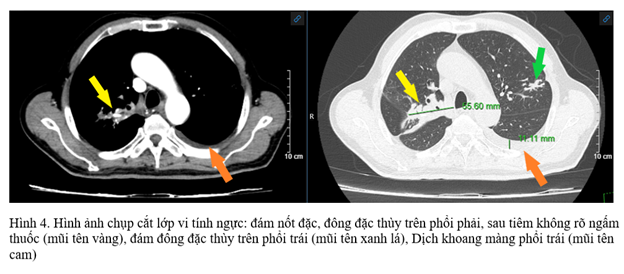

- CLVT lồng ngực: Hình ảnh đám nốt đặc, đông đặc, vài dải xơ thùy trên phổi phải có cấu trúc tăng tỷ trọng hình que bên trong. Đám đông đặc thùy trên phổi trái. Dịch khoang màng phổi trái.